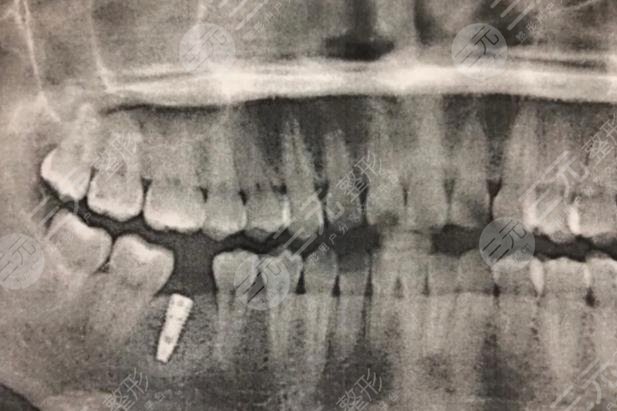

My teeth were decayed because of the insect teeth, and then they couldn't be repaired, so they had to be extracted, and then because there was a missing one in the back, the tooth was very troublesome to use, so I did the tooth prosthesis, but because the tooth prosthesis is not very strong, every time I eat something, it is also very troublesome, and it is easy to fall off, so I had the intention of doing dental implants at that time, and later under the introduction of friends, I heard that the dental implant technology of Jiujiang Zhongshan Dental Clinic is still very trustworthy.

Then I went to the hospital for registration, the whole process is still very good, there is no bad feeling, the doctor who gave me oral implants is very cautious, because dental implants can not be done at one time, so he did several teeth for me before and after, the experience is very good, the operation is done for me after the teeth are cleaned, do not worry about the problem of infection, and the hospital's diagnosis and treatment environment is also relatively high-end, so in the process of doing dental implant surgery projects, it will also make people more soothing.

Now the dental implant has been more than a year, there are no other problems during the use, and it is no different from other real teeth, if I don't say that this tooth is an implant, friends basically can't see it, and the hardness of this tooth is much better than the degree of the previous tooth inscar, I can eat some harder food, but it is very hard or don't eat, or I want to thank the doctor of the Zhongshan Dental Clinic in Jiujiang City, so that I have such a good tooth.